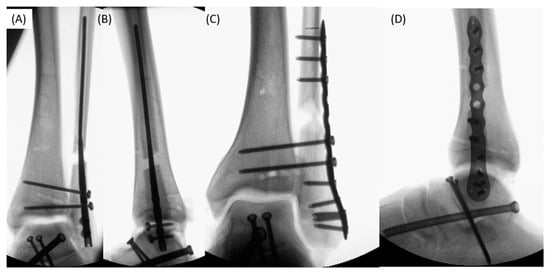

2.2. Standardized Instability and Fixation